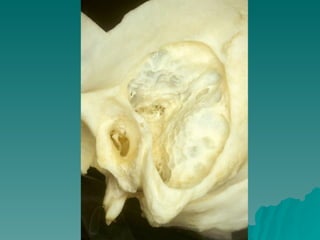

OTITIS MEDIA CRÓNICA Patogenia del colesteatoma

OTITIS MEDIA CRÓNICA Histología del Colesteatoma

OTITIS MEDIA CRÓNICA